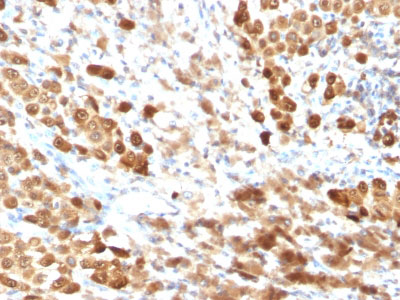

Formalin-fixed, paraffin-embedded human Melanoma stained with S100A1 Monoclonal Antibody (SPM354). |